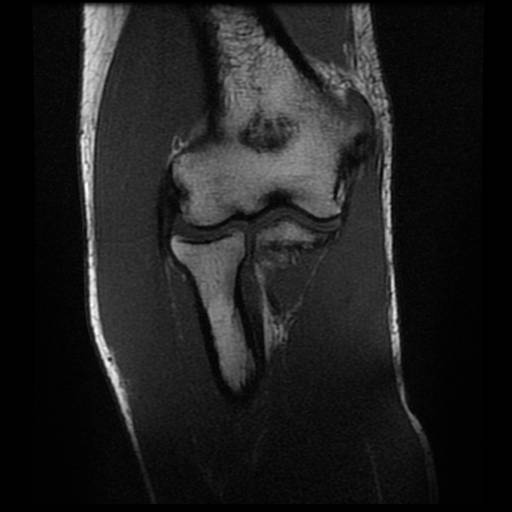

白色文字(排除指定关键词) Imaging Anatomy: interactive PACS-like atlas of radiological anatomy

解剖学模块